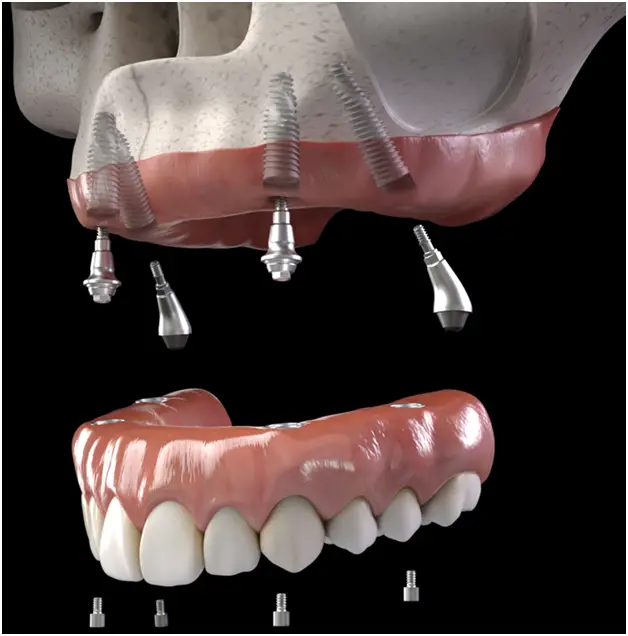

All-on-X implants are a modern dental technology that uses strategically placed dental implants to support a full set of prosthetic teeth. Unlike traditional dentures, All-on-X implants are fixed to the jawbone, providing a much more secure and permanent solution. These implants are specifically designed for patients with insufficient bone density, so they don’t require a bone graft, making the procedure less invasive and more convenient.

The term "All-on-X" refers to the number of implants used, which can vary between four to six implants depending on your individual needs. These implants provide a strong foundation for a custom-made denture, which is securely attached to the implants. The result is a restoration that looks and feels just like your natural teeth, without the hassle of adhesives or worrying about them slipping.

- Implant Placement: On the day of the procedure, the implants are strategically placed into your jawbone. We use advanced technology to ensure that the implants are positioned precisely for the best results.

- Placement of Final Prosthesis: Once the implants are fully integrated into the bone, we will place your custom-made dentures onto the implants. The result is a natural-looking, functional set of teeth that will last for years.